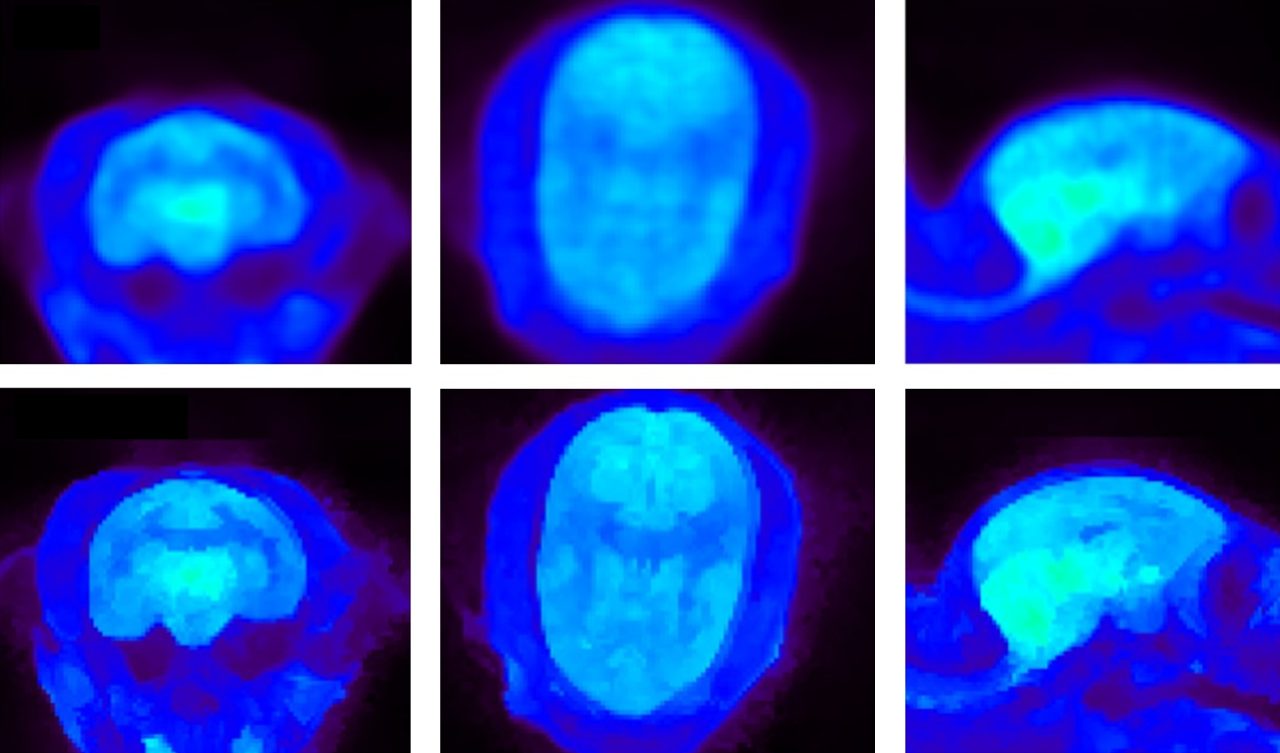

Improved PET studies

• Comprehensive isotope database for simple selection of most common isotopes

• Bowsher Prior reconstruction leveraging anatomical MRI to improve the PET image

• ⁠Expanded suite of color lookup tables including the Cold color palette for enhanced interpretability

Marmoset brain imaging with PET FDG. Top: MAP reconstruction. Bottom: Bowsher Prior reconstruction, an advanced PET reconstruction algorithm. Courtesy: S. Valable and M Naveau, Cyceron, Caen, France.